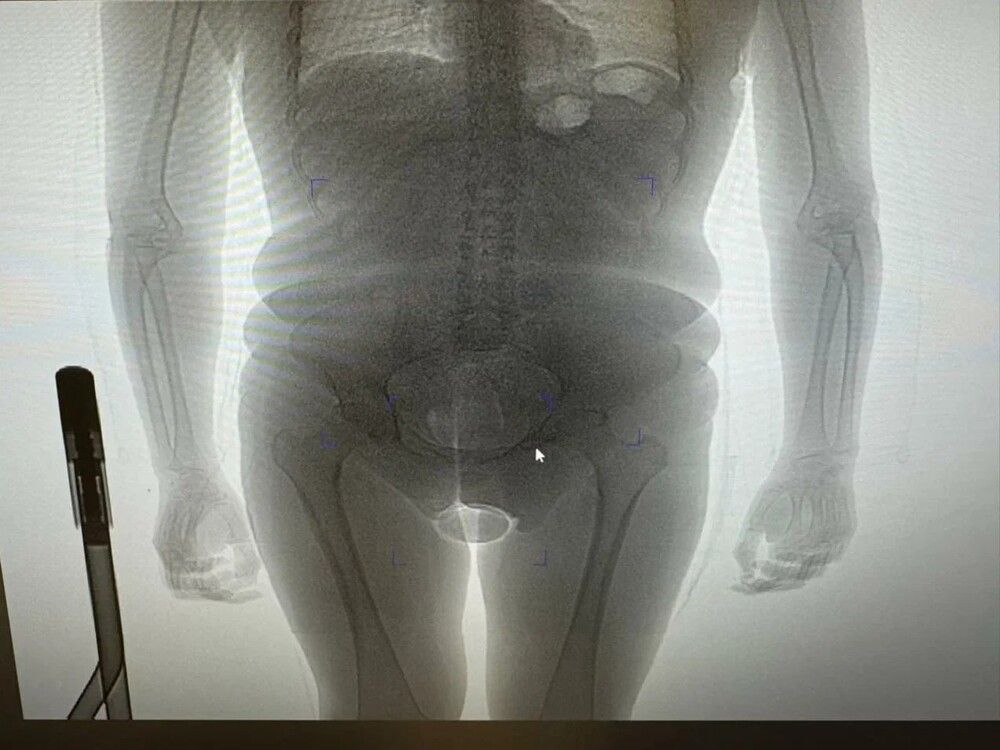

Сотрудники домодедовской таможни задержали 22-летнюю гражданку Бразилии, попытавшуюся провезти в России партию кокаина внутриполостным способом. Отмечается, что пассажирка прибыла в Россию из Дубая и была остановлена сотрудниками ФТС на "зеленом" коридоре.В ходе досмотра таможенники обнаружили два презерватива с порошкообразным веществом. Один был спрятан в нижнем белье пассажирки, а второй - в естественном отверстии. Обнаружить его помог рентген.Задержанная сразу призналась, что пыталась провезти кокаин, а контрабандой наркотиков занялась, чтобы заработать денег - за это ей якобы заплатил неизвестный мужчина. Вскоре экспертиза подтвердила, что в презервативах находился кокаин общей массой 250 граммов.